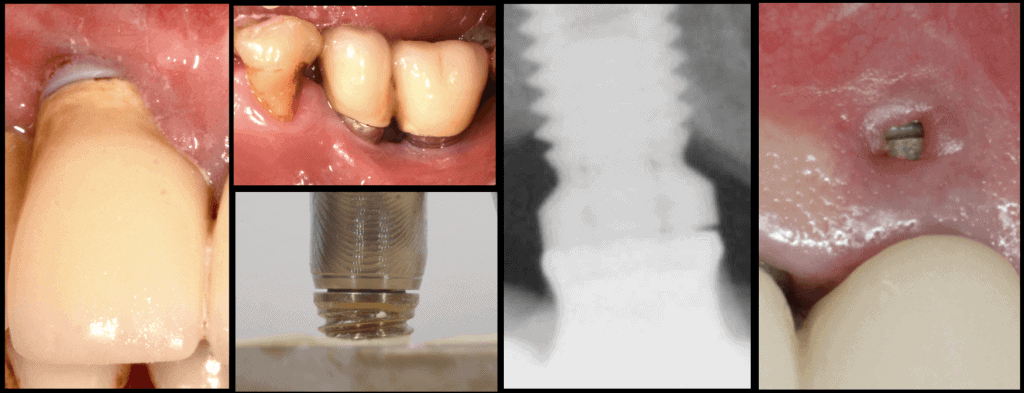

Nr. 3: Size matters!

The Supracrestal complex is defined by the soft tissues and as such , the vertical height, the width (thickness) and overall morphology / consistency of the soft tissues is critical for the final long term success of our outcomes! A critical pre-assessment therefore includes the questions:

– what are the essential soft tissue outcomes for long term health?

– how likely are we with our intervention to ensure the soft tissue outcomes we need?

– how to design our intervention so as to achieve this in the most simple and predictable way?

Nr. 4: Position yourself for success !

The correct 3-dimensional implant position is essential for everything else to work Compromised implant 3D position is the “root of all evil” leading a chain reaction of compromise in the restorative design and finally maintainability. Knowing the limitations from the beginning and decide the strategy that will allow us the perfect placement is an art and a science combined.

Nr. 5: Stay in shape !

The “emergence profile” is a key for long term success and its optimal shape and size is crucial. Depth or height, Concavity or Convexity, angles of emergence, these are all design features we need to plan in advance before the implant is even placed. Otherwise, compromise and trouble is inevitable.